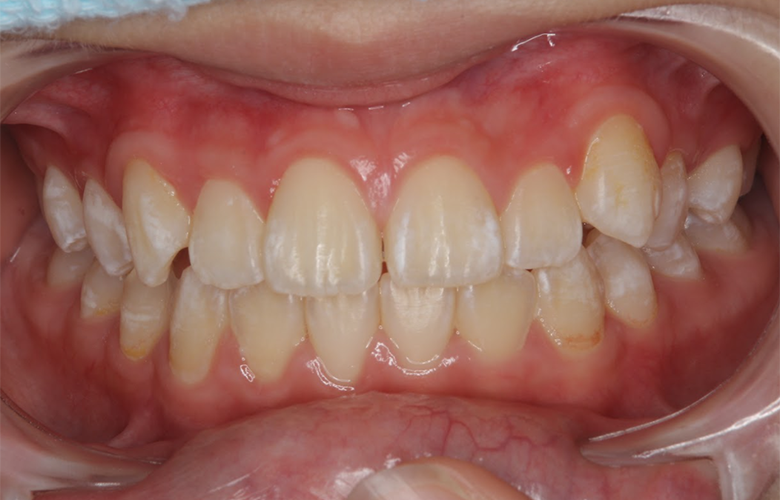

治療後 ![]() |

歯列の幅が広がり、永久歯が萌出するためのスペースが確保されました。前歯の重なりも改善し、咬合バランスも安定しています。今後永久歯列完成後の叢生改善については、必要に応じてⅡ期治療(成人矯正)で最終的な歯列調整を行う可能性があります。 |

小児矯正のⅠ期治療は、歯を無理に並べることではなく、顎の成長を利用して永久歯が並ぶスペースを確保することが大きな目的です。本症例のように混合歯列期に適切な歯列弓を形成することで、将来的な歯列不正のリスクを軽減することが期待できます。歯並びが気になるお子様は、早めの相談をおすすめします。 |